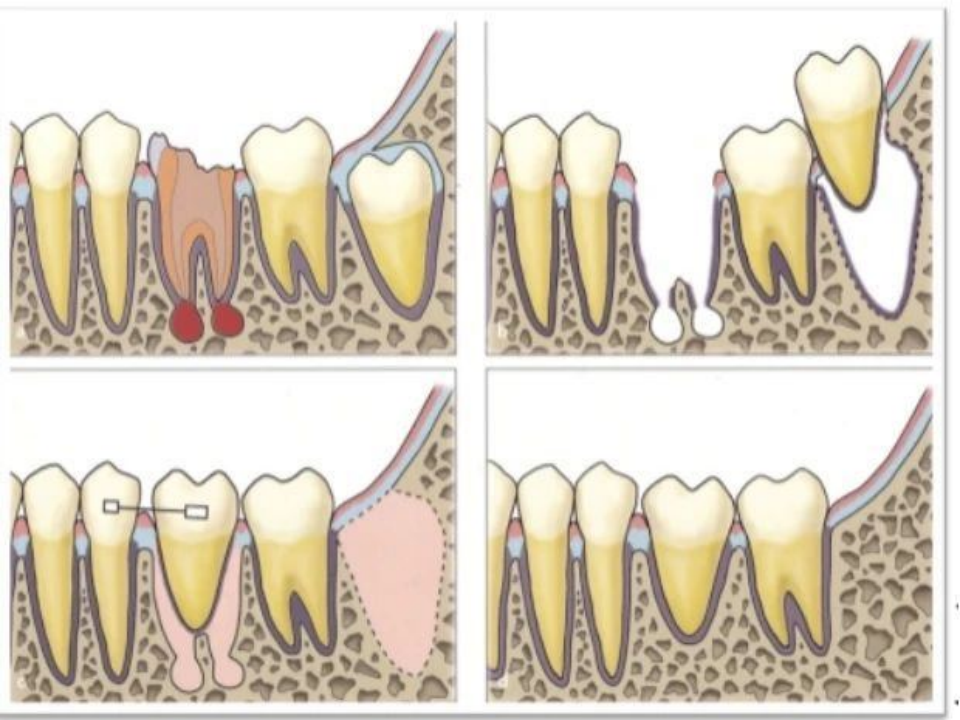

而自体牙移植,是指将患者自己的牙齿从一个位置移植到另一个位置的手术过程,常见于将埋伏、阻生或废用的智齿转移到其他需要拔牙部位或缺牙部位。

与传统方式不同,自体牙移植是使用自己的真牙来修复缺牙。

自体牙移植示意图